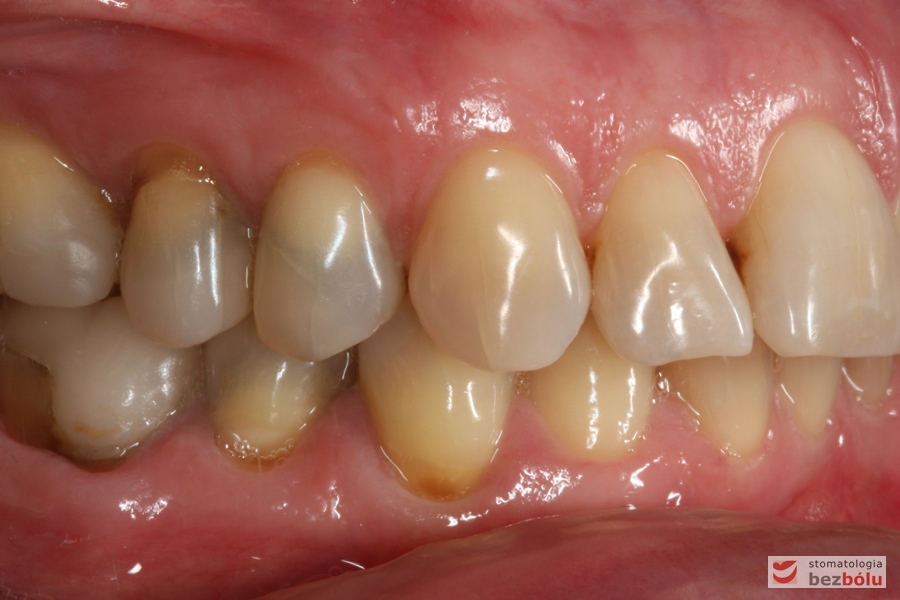

Do naszej placówki zgłosiła się starannie planująca swoje działania Europejka, mieszkająca na stałe w Kotlinie Jeleniogórskiej. Jej oczekiwania dotyczyły bardzo metodycznie zaplanowanego planu leczenia. Celem jaki postawiła przed naszym zespołem lekarzy było wyeliminowanie wszystkich wątpliwych i nierokujących wypełnień, a także poprawa estetyki w zakresie lewego siekacza centralnego w szczęce. Został rozpisany blisko dwuletni plan wymiany zużytych i nieszczelnych wypełnień amalgamatowych i kompozytowych. Zaplanowano również przygotowanie endodontyczne wybranych zębów w szczęce i żuchwie, a także zaopatrzenie w inlay’e porcelanowe i korony ceramiczne wykonane w systemie e-max.